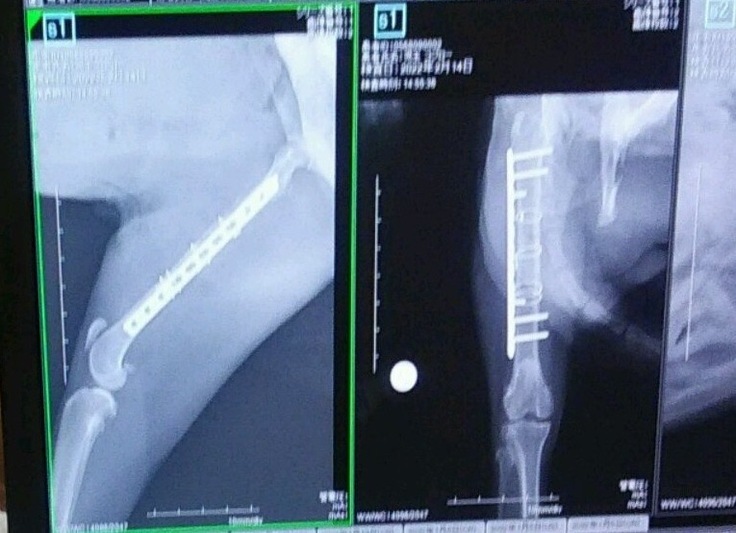

レントゲンで手術前と後の状態を見せていただきました。プレートを入れて固定しています。

手術後血尿は止まっており、食欲もあるそうです。面会に行くとホッとしたようなお顔を見せてくれます。

術後のレントゲン撮影に行ってきました。